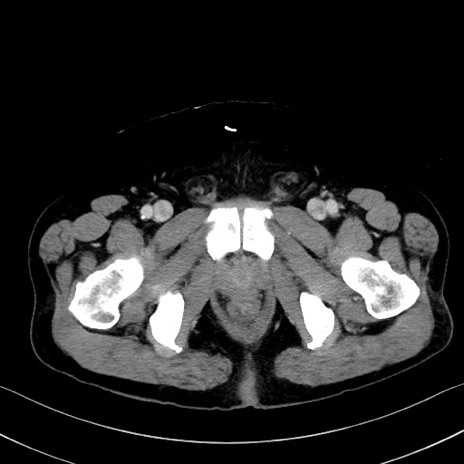

症例35(横断像)

【症例】70歳代 男性

【主訴】腹部膨満、嘔吐

【現病歴】昨日より腹部膨満感出現。本日増悪し、仙痛出現。嘔吐あり、受診。

【既往歴】糖尿病、胆摘後

【身体所見】BP 149/80mmHg、HR 74/min、BT 35.9℃、腹部:膨満、軟、圧痛なし。腸雑音減弱あり。上腹部正中切開瘢痕あり。

【データ】WBC 13500、CRP 1.72